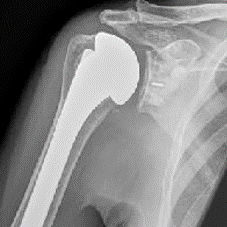

Verder worden tijdens de ingreep de andere pezen gespaard en de gewrichtsoppervlaktes vervangen door een polyethyleen pannetje dat wordt gecementeerd en een nieuwe bol, bestaande uit metaal die wordt vastgekneld in de vroegere bol of op een steel die gefixeerd wordt in het bot.